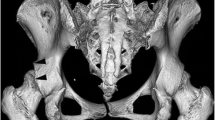

Sharp’s angle

This angle was described by Sharp in 1961 for the assessment of hip dysplasia [12]. A reference line was drawn between the inferior points of the teardrops on AP pelvis radiographs. The angle was formed by this reference line and a line connecting the inferior point of the teardrop and the lateral edge of the acetabulum (Fig. 1).

Acetabular depth-to-width ratio (ADR)

The acetabular depth and width were measured on AP pelvic radiographs, as described by Heyman and Herndon in 1950 [4]. The length of a line connecting the lateral osseous acetabular margin and the lower end of the teardrop defined the width of the acetabulum. This teardrop is often more accurately defined than the lower acetabular margin. The depth was defined as the distance from the width line to the deepest point of the acetabulum (Fig. 1).

Lateral acetabular inclination

The lateral acetabular inclination was introduced by Cooperman et al. [13] in 1983 and later applied by Grzegorzewski et al. [15] for children with Perthes’ disease. It was recorded as down, horizontal or up, depending on whether the lateral lip of the acetabulum was below, horizontal or above the weight-bearing dome of the acetabulum, respectively (Fig. 2).